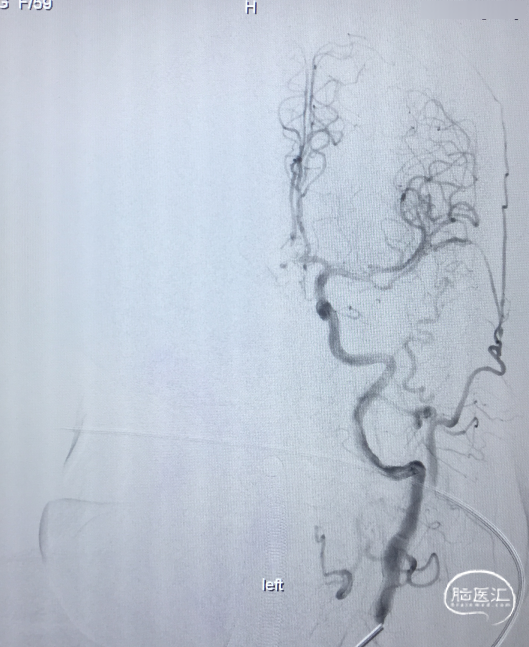

术前DSA 3D:左颈内动脉正侧位及工作位,前交通动脉瘤,约4×8mm,颈宽约6.5mm,形态宽颈、分叶。前交通动脉及大脑前动脉A1、A2直径约2mm。

术前DSA:LICA正侧位及工作角度造影显示前交通动脉瘤

术前DSA:RCCA正侧位造影